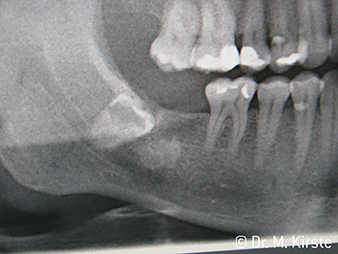

W&H рентгенова снимка

Фиг. 6:

Пример с пациент: Разместеният 48-и зъб...